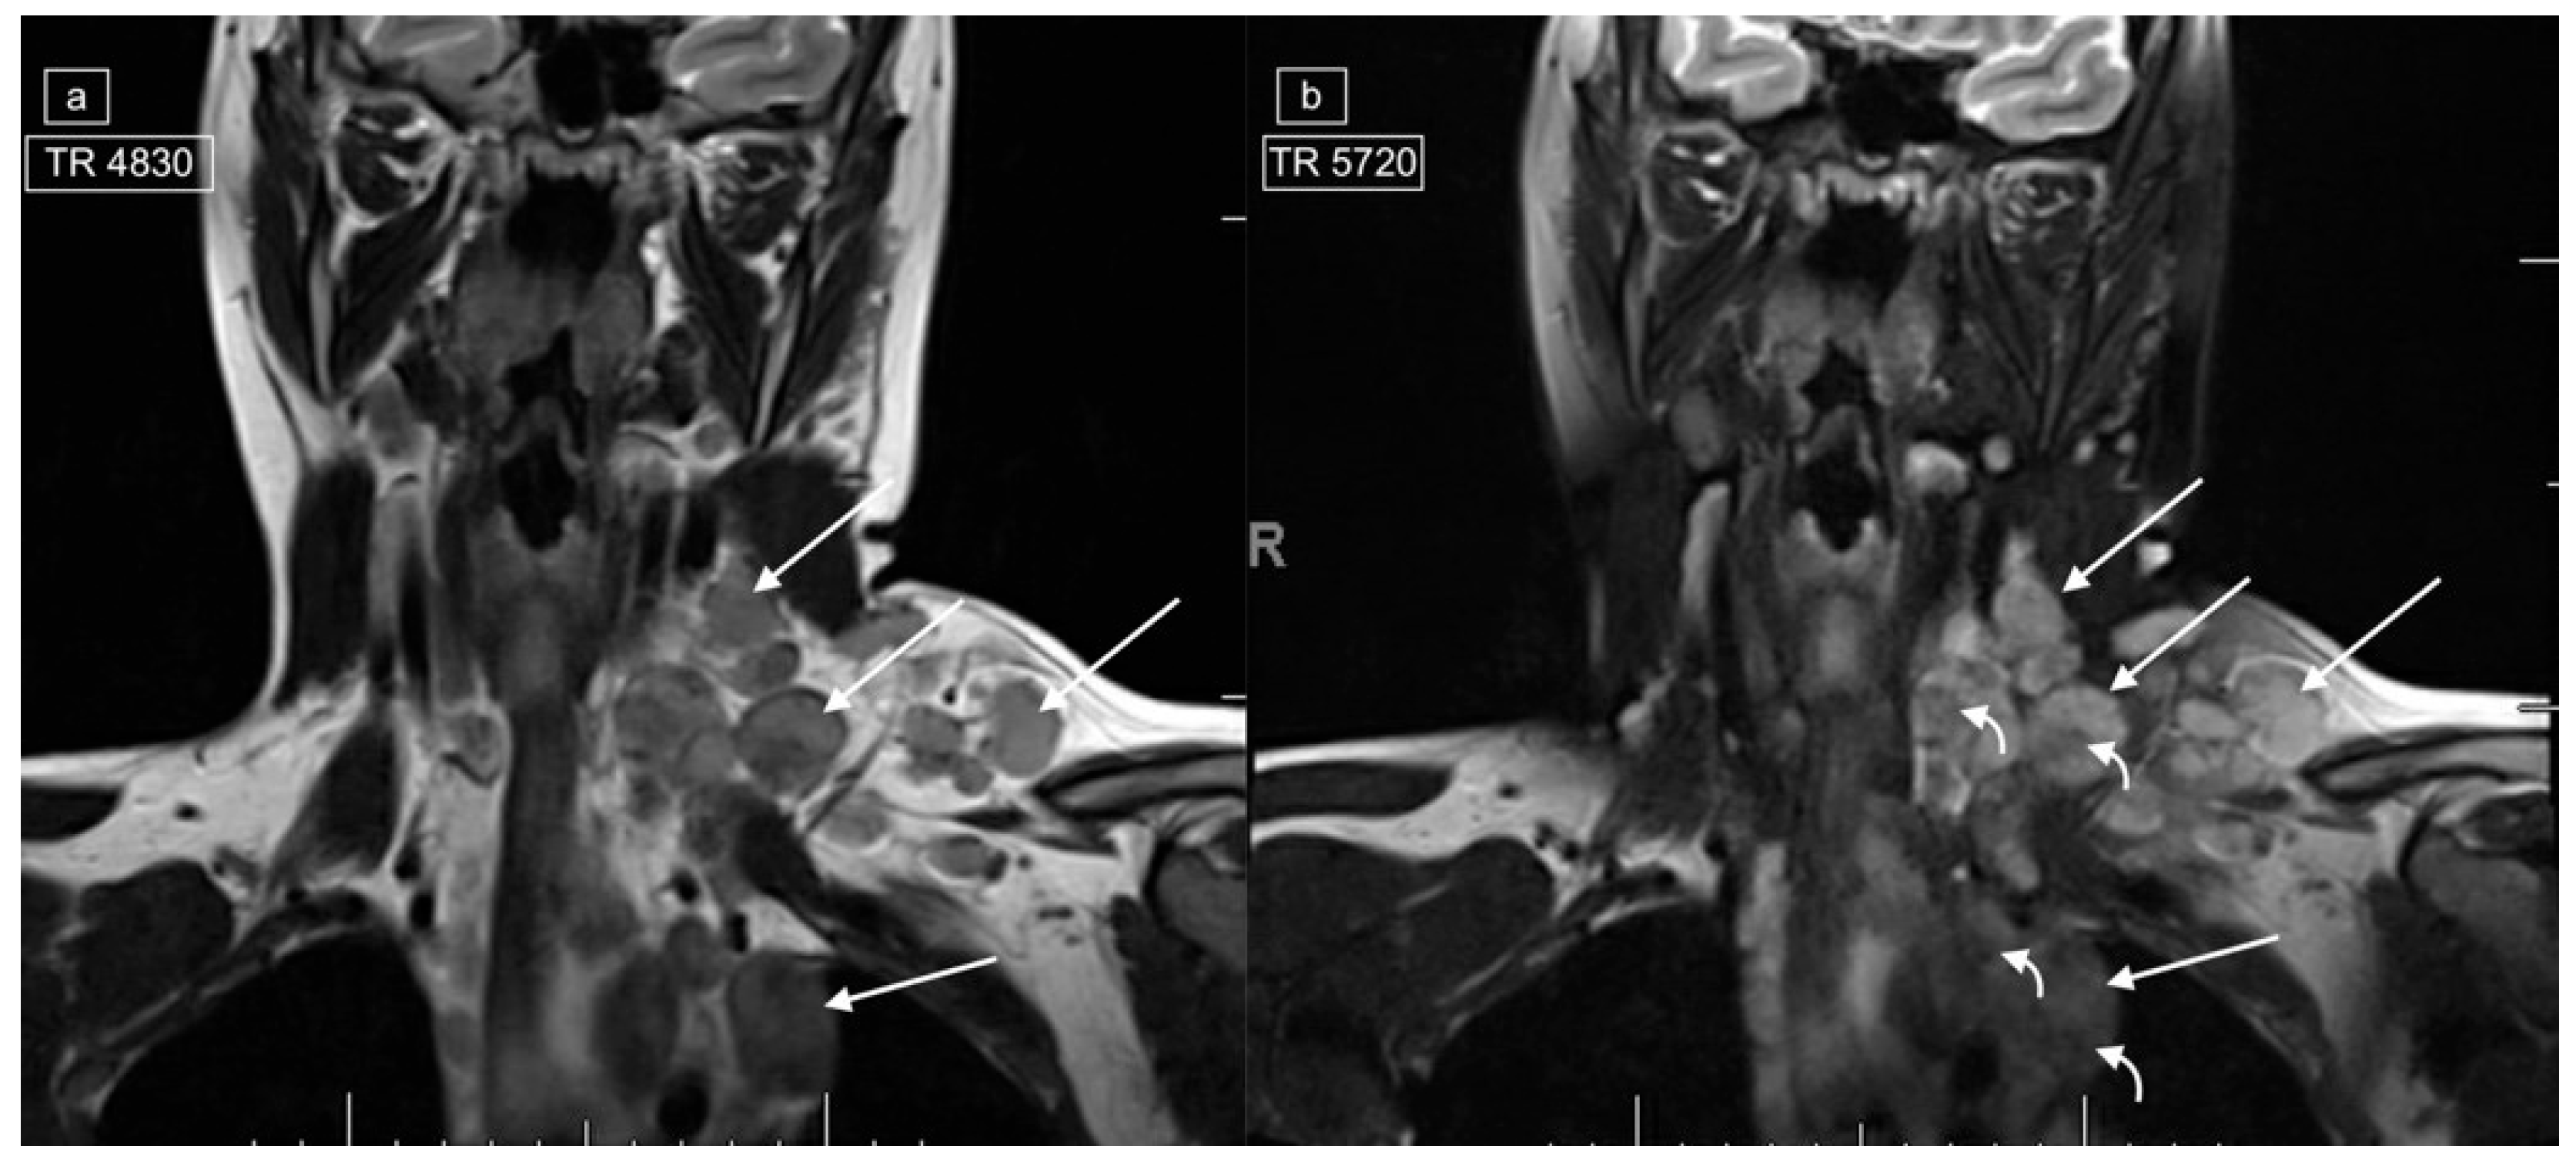

Figure 4.

Images demonstrating technical reasons for lower T2 signal of lymphadenopathy. MRI of the cervical region in a 12-year-old male with a histologic diagnosis of nodular sclerosing Hodgkin lymphoma. The right lower cervical lymphadenopathy (arrows) demonstrates low signal on T2 (a) and higher signal on STIR (b), with only mild enhancement on post-gadolinium T1-weighted imaging (c).